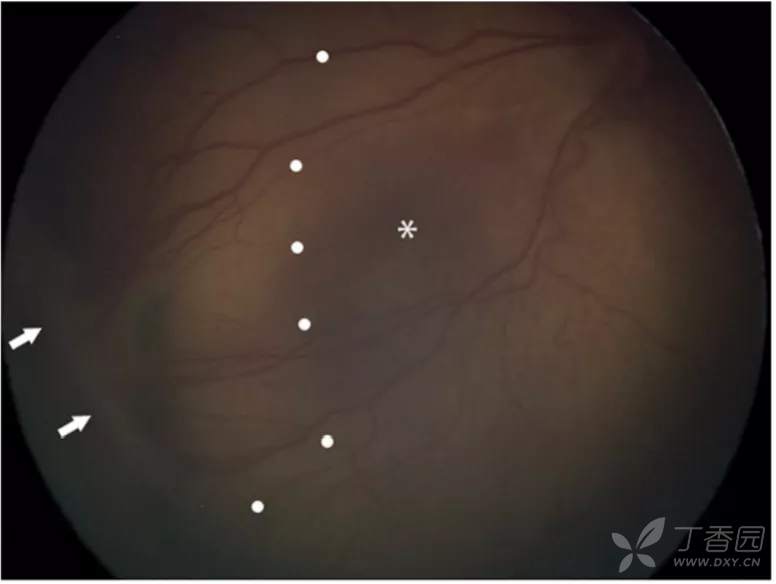

图. 4A期, 视网膜外新生血管牵引可导致视网膜隆起(白点),中心凹(星号)未见脱离,视网膜外新生血管(白箭)可能较脱离区更周边。